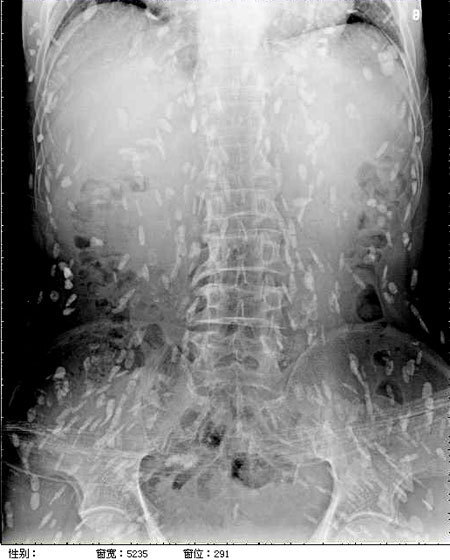

이 기생충들이 뇌조직으로 침투할 경우 생명에 위험을 초래할 수 있습니다. 회를 섭취한 남성의 사례에서도 복부통증과 피부가려움 등의 증상이 나타나, 엑스레이 결과 전신에 기생충이 퍼져 있는 것이 확인되었습니다. 따라서, 이러한 기생충에 감염될 경우 조기에 발견하고 치료하는 것이 매우 중요합니다.

마지막으로, 위에서 언급한 엑스레이 사진과 관련된 환자의 경우, 의료진은 해당 환자가 특별한 치료를 받지 않았다고 밝혔습니다. 만약 머리, 척수, 눈에 이상이 없다면 치료를 받을 필요가 없다고 말하고 있습니다. 또한, 사진 속의 유충들은 석회화되어 생존할 수 없는 상태이므로 특별한 조치가 필요하지 않다고 설명되었습니다. 그러나 해당 환자의 뇌에 낭종이 있는지 확인하기 위해 MRI 검사를 기다리고 있다고 전했습니다.